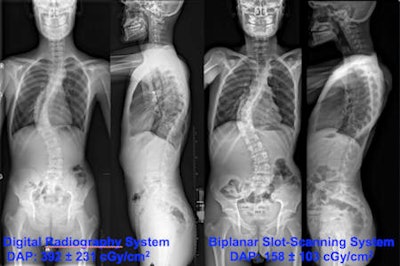

Because of its design, the biplanar x-ray system enables diagnostic quality images to be acquired at lower radiation levels. As a result, the dose area product was lower than that of the standard DR system. A whole spine image generated a dose area product of 158.4 cGy/cm2 compared with 392.2 cGy/cm2 when a standard DR system was used.